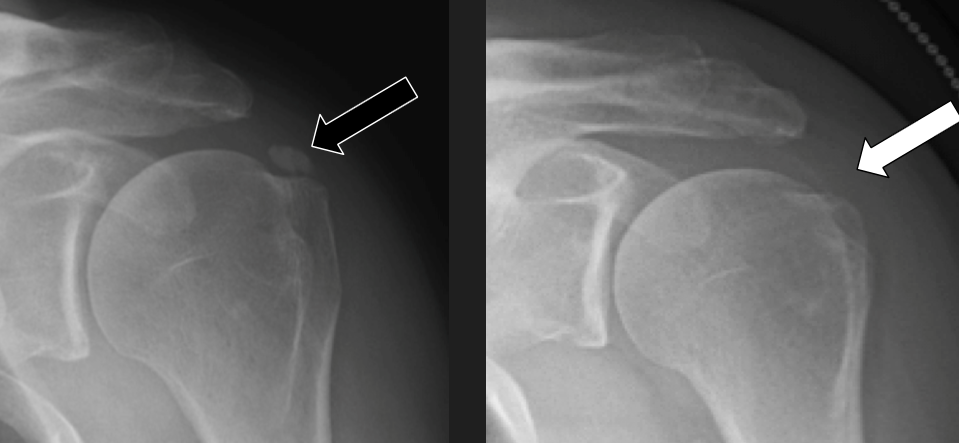

Diagnoza se v tem primeru najbolje pokaže pri slikanju z rentgenom, saj se kalcinacije vidijo in oblikujejo podobno kot kosti. Proces hipertrofije kosti kot je recimo Osgood – Schlatterjev sindrom v kolenih, kjer se poveča izrastek, kamor se pripenja sprednja stegenska mišica (tibialna tuberoziteta) in je strukturno zelo podoben kalcinacijam v rami.

Kalcinacija rame oz. kalcijevi kristalčki se najbolj jasno pokažejo pri slikanju z rentgenom. Prisotnost značilnih simptomov in vidni kalcinati na rentgenski so ključni pri postavitvi diagnoze. Pri diagnostiki nam lahko pomaga tudi ultrazvok, s katerim lahko ocenimo velikost kalcinatov in v kateri fazi kalcifikacije je pacient. Če smo v dvomu, ali gre res za kalcinacijo rame ali za kakšno drugo stanje s podobnimi simptomi (npr. ruptura rotatorne manšete ali zamrznjena rama), se lahko opravi tudi magnetno resonanco, s katero lahko preverimo potencialne poškodbe v mehkih tkivih.